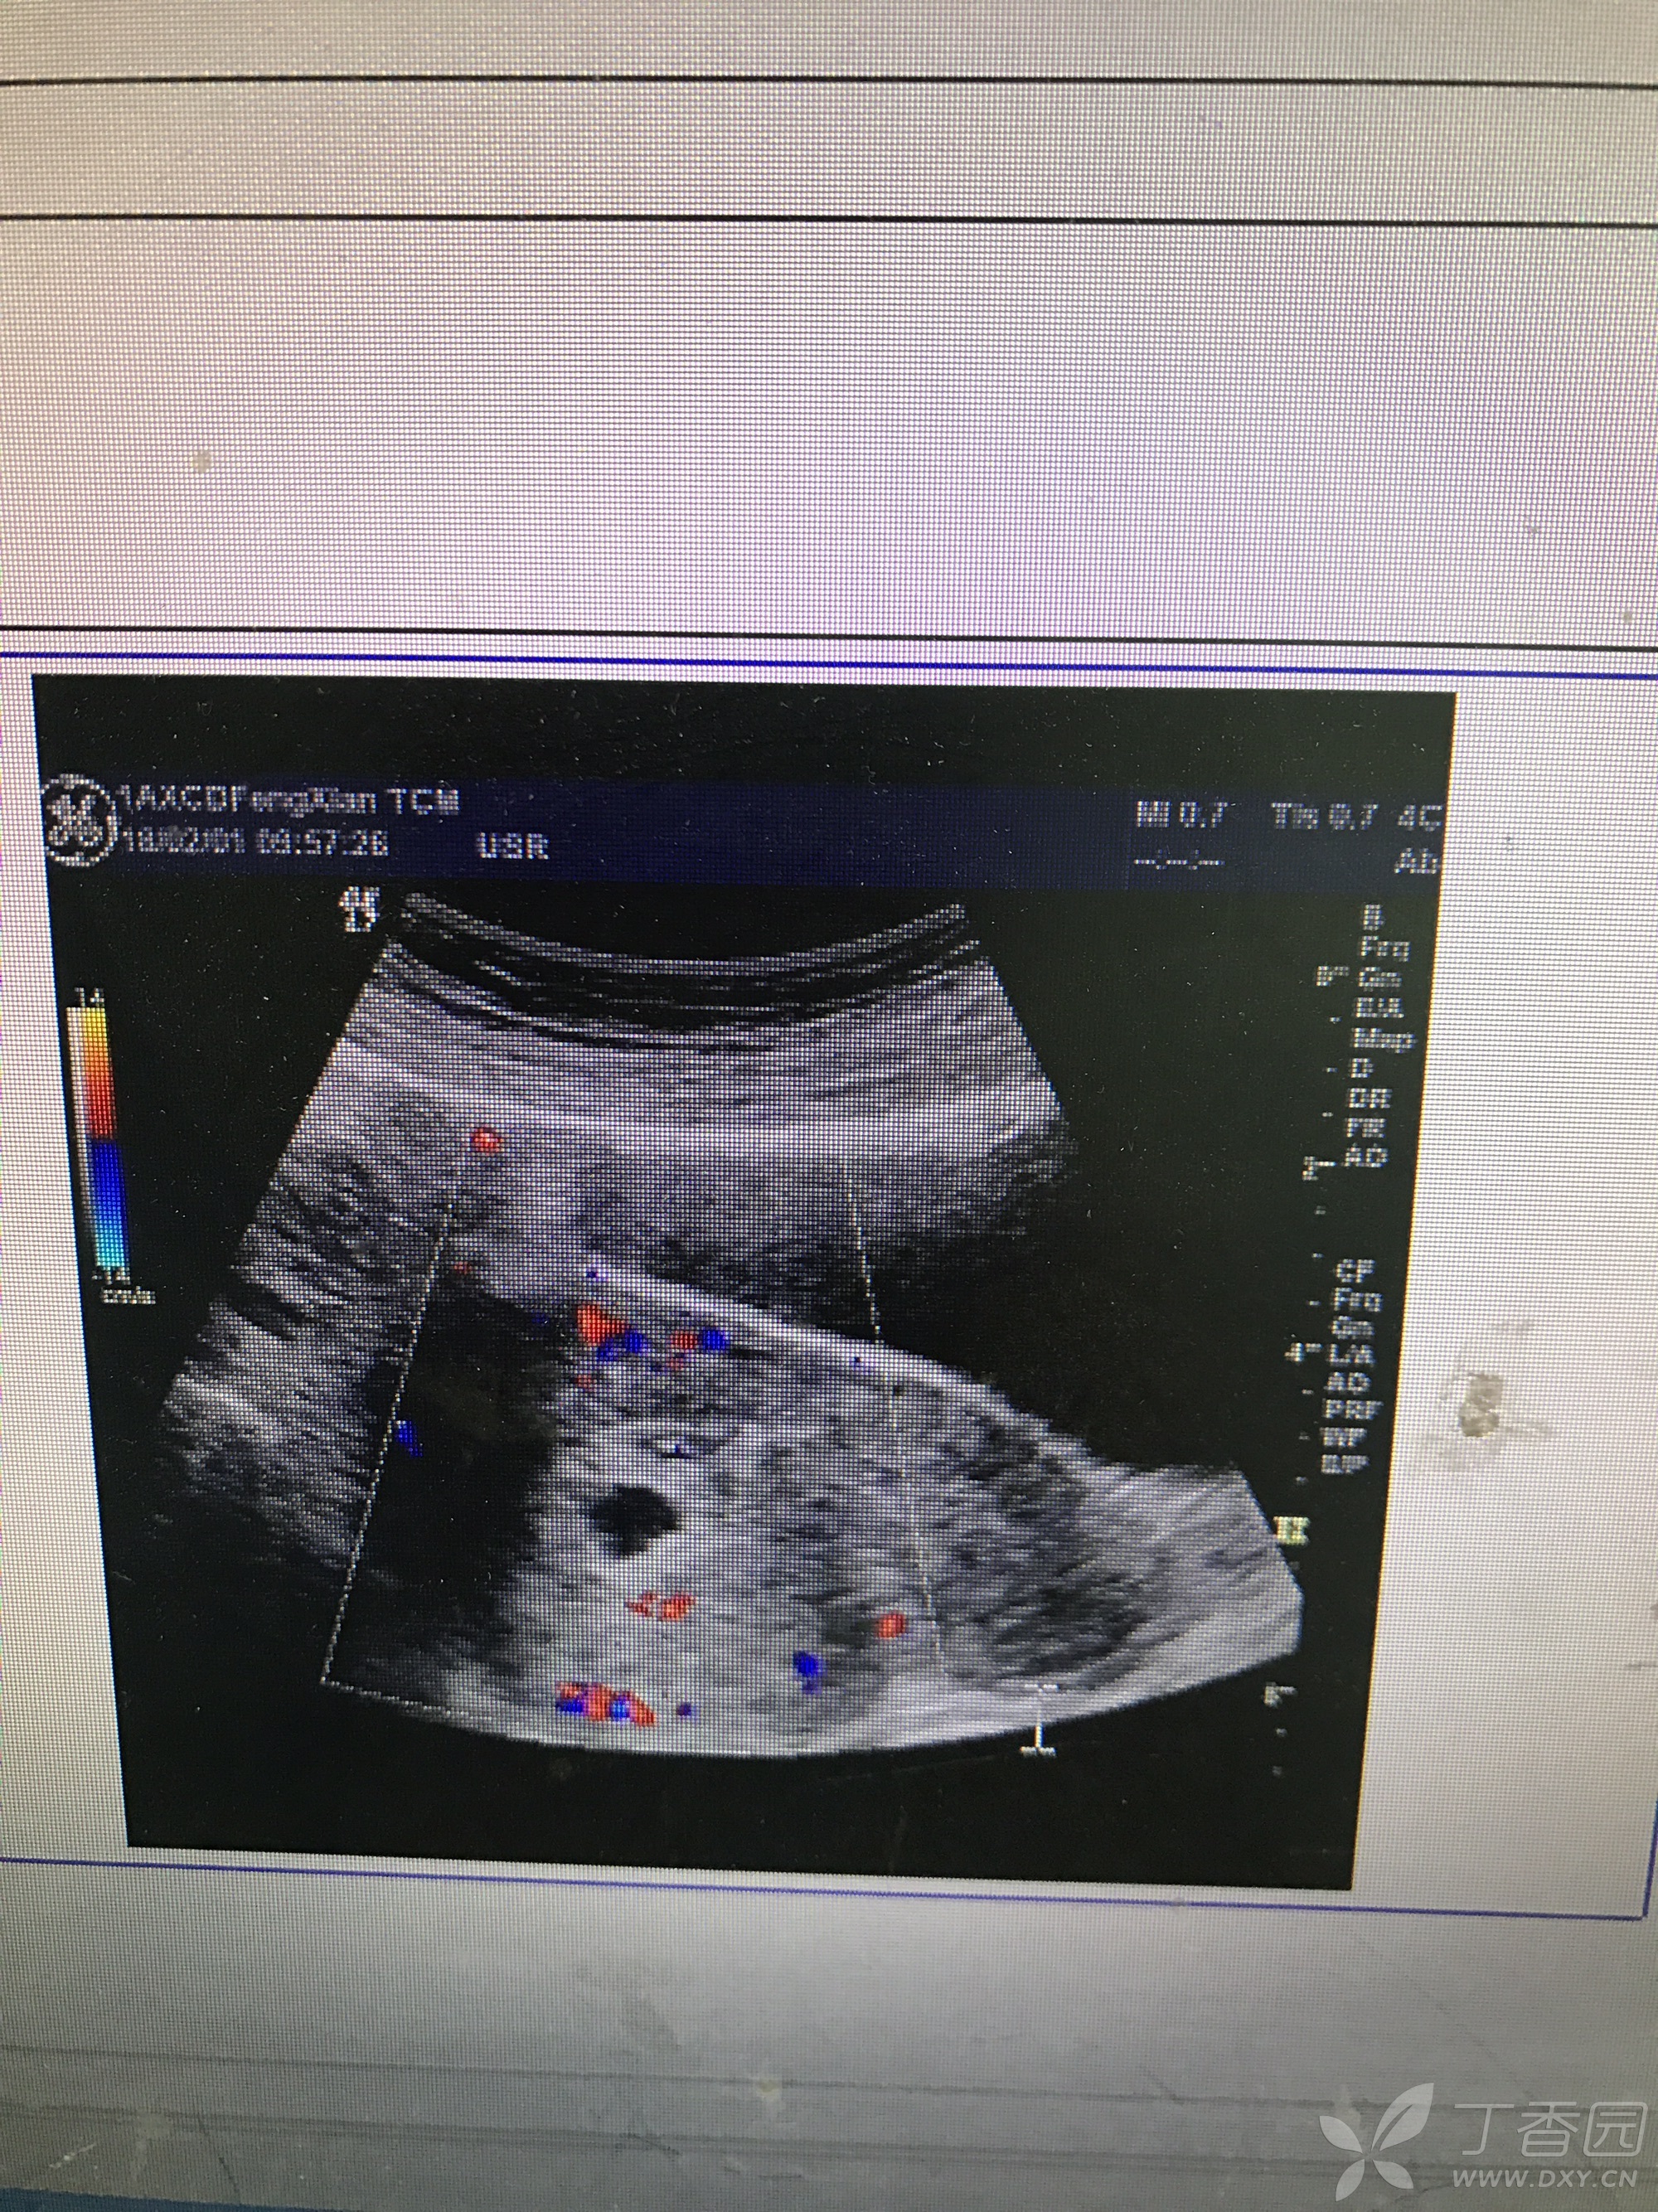

超声孕囊旁积血

超声孕囊旁积血,长孕囊和圆孕囊图片

早孕 宫内积血 超声医学讨论版 爱爱医医学论坛

孕囊旁积血又长大了,愁*了